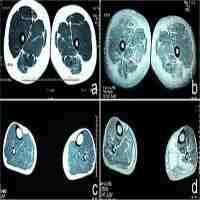

| Abstract | In this study, we aim to investigate the clinical features and Mutations of sodium channel α-subunit (SCN4A) genes in Chinese patients with normokalemic periodic paralysis (normoKPP).Six unrelated Chinese families with normoKPP were analyzed in clinical features. Genomic DNA was extracted from peripheral blood leukocytes and amplified with PCR. We screened all 24 exons of SCN4A gene with denaturing high performance liquid chromatography (DHPLC) technology, and then sequence analysis was performed in those who showed heteroduplex as compared with unaffected controls.The laboratory tests were within normal ranges. Electromyograms and electrocardiograms were normal. One muscle biopsy was performed with the patient in family 4 after a brief attack of normoKPP. Examination of light microscopy showed no changes, but electronic microscopy showed occasionally degenerating myofibers. The mutations of SCN4A genes were as follows: ➀ Met1592Val occurred in family 1. ➁ Val-781-Ile occurred with the patient and her father in family 4. ➂ Both the patients had a novel mutation g2101a predicting the amino acid exchange Arg675Gln in family 5, which may be a disease-causing mutation.In addition to Val-781-Ile and Met1592Val, the mutation g2101a (Arg675Gln) may be the novel mutation of SCN4A genes in Chinese patients with normoKPP. |